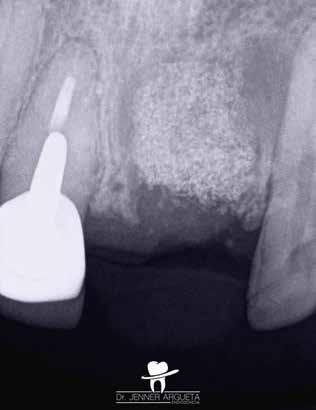

1. a-n. ábrák: Preoperatív CBCT-felvétel a bal alsó 6-os (3.6) fogról. Az axialis (a), coronalis (b) és sagittalis (c) nézeteken a mezialis és distalis gyökerek apicalis harmada körül sugáráteresztő zóna és ép buccalis corticalis csont látható. Egy olyan sablont terveztünk, amely jelezte a csontablak határait az apicalis terület pontos elérése érdekében (d). A mikrosebészeti bevatkozás során a sablont a helyére illesztettük (e), a csontablak határait megjelöltük (f) egy Piezotome CUBE LED kézi-darabba fogott fűrésszel, majd kivágtuk és eltávolítottuk (g és h) az apicalis területhez történő hozzáférés, illetve a mezialis és distalis gyökerek rezekciójának, retrográd preparációjának és retrográd gyökértömésének elvégzése érdekében (i). Végezetül a csontablakot visszaillesztettük és kollagén szivaccsal stabilizáltuk (j). A műtét után közvetlenül készített röntgenfelvétel a 3.6-os fogról (k). A kétéves kontroll során készített CBCT-felvétel: axialis (l), coronalis (m) és sagittalis (n) nézetek.

Egy 63 éves páciens korábban már kezelt bal alsó első nagyőrlőfogából (3.6) eredő mérsékelt fájdalom miatt kereste fel rendelőnket. A kórtörténetében panasza szempontjából releváns információ nem szerepelt. Az elkészült CBCT-felvételen a korábbi kezelések során észre nem vett, jelenleg feltáratlan meziobuccalis csatornát, valamint a mezialis és distalis gyökerek körül kialakult periapicalis elváltozást, és ezt a léziót borító intakt buccalis corticalis csontlemezt láttunk.

A fog revideálását és újbóli gyökértömését két ülésben végeztük el. A régi gyökértömés eltávolítását, valamint mindhárom gyökércsatorna megmunkálását és fertőtlenítését követően kalcium-hidroxid alapú gyógyszeres zárást helyeztünk a gyökércsatornákba. A gyökértömés egy héttel később került behelyezésre. A páciens panaszai két hónap elteltével sem szűntek.

Klinikai vizsgálat során vertikális kopogtatási érzékenységet jelzett. A fog körül mérhető szondázási mélység és a fogmobilitás fiziológiás volt. A CBCT-felvételen nem észleltünk a csontos regeneráció megindulására utaló jeleket (1. a–c. ábrák). A korábban gyökérkezelt, gyökértömött és revideált 3.6-os fog esetében az alábbi diagnózis került felállításra: periodontitis periapicalis symptomatica. A panaszokat okozó fog további ellátása során navigált endodonciai mikrosebészetet kívántunk alkalmazni. Az alsó állcsontról intraorális szkent (TRIOS, 3Shape) készítettünk, és a felszíni topográfiát tartalmazó STL fájlt, valamint a CBCT-felvétel készítése során nyert DICOM fájlokat a Blue Sky Bio szoftver segítségével egyesítettük. A sebészi sablon megtervezésére az így kapott háromdimenziós képet használtuk. A sablon kialakítása során arra törekedtünk, hogy a sablon egyértelműen meghatározza a gyökércsúcsi terület eléréséhez szükséges csontablak határait (1. d. ábra)

A beavatkozás során helyi érzéstelenítésben teljes vastagságú mucoperiostealis lebenyt képeztünk, és a sablon segítségével bejelöltük a preparálandó csontablak határait. Az ablak széleinek megfelelően Piezotome CUBE LED kézi-darabbal (ACTEON) a kortikális teljes vastagságában vágást ejtettünk, majd az így kapott csontlemezt (ablakot) eltávolítottuk (1. e–h. ábra), és ezt követően steril fiziológiás sóoldatba helyeztük. A rezekció elvégzését követően (1. i. ábra) a mezialis csatornákat ultrahangos eszközök segítségével (NSK) retrográd irányból preparáltuk, majd az így kialakított mélyedésbe retrográd gyökértömést készítettünk. A tömés anyagául az EndoSequence BC RRM Fast Set Putty-t (Brasseler) választottuk. A tömés elkészítését követően a csontablakot visszaillesztettük, és a stabilizálása érdekében a vágásoknak megfelelően kialakult résekbe kollagén szivacsokat (Collagen Tape, Zimmer Biomet) helyeztünk (1. j-k. ábra). A lebenyt 6/0-s Prolene varratokkal (Corpaul) rögzítettük.

A kétéves kontroll során elvégzett klinikai és radiológiai vizsgálat (CBCT-felvétel) a periapicalis elváltozások megszűnését és a corticalis csontállomány tünet- és szövődménymentes gyógyulását